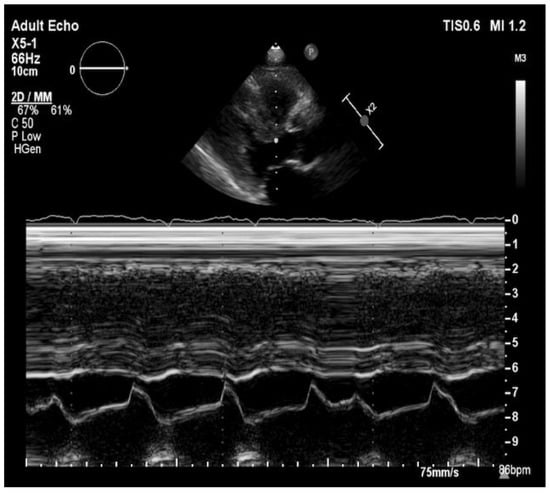

The ultrasonography showed bilateral pleural effusion. MRI examination of pelvis confirmed massive edema of retroperitoneal and subcutaneous adipose tissue and inguinal lymphadenopathy. The echocardiographic examination (Figure 1) showed small dimensions of hearth cavities, the interventricular septum thickened to 22 mm, with the streaky brightening in the center, without significant valves disorders and right ventricle hypertrophy. The left ventricular end-systolic diameter was 12 mm and the left ventricular end-diastolic diameter was 24 mm, moreover, there was bilateral pleural effusion and 4 mm of fluid behind the left atrium. The left ventricle ejection fracture was preserved (55%). Electrocardiographic examination showed QS system in III, aVF, V1 and V2 and low QRS voltage in limb leads, Qtc was 503 ms.

Figure 1. Transthoracic echocardiography in long parasternal view/M-Mode showing left ventricular hypertrophy.